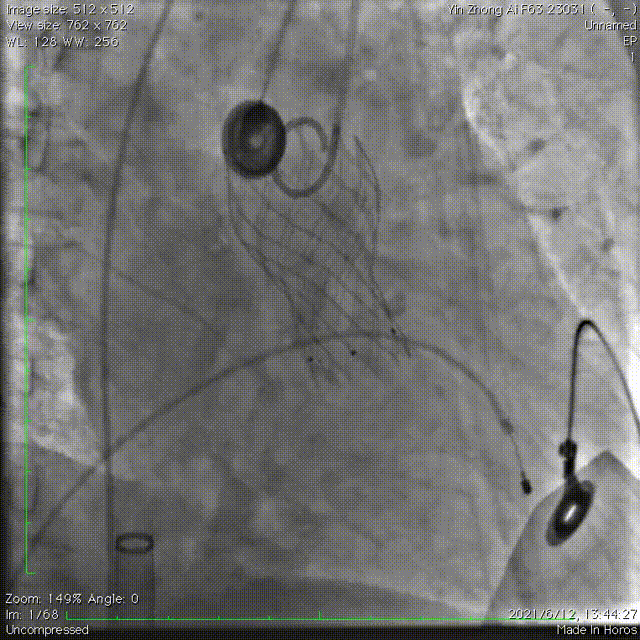

主动脉根部造影可以清晰显示瓣叶钙化及活动受限。

选用AL2.0导管配合泥鳅导丝成功跨瓣。

采用右冠guidezilla+预置支架保护,在右足Double-S体位下,选择Venus-A Valve 23瓣膜精准释放,跨瓣后及释放过程中患者持续低血压,释放2/3后血压仍无法恢复,调整好JR指引导管和guidezilla深度后,完全释放瓣膜。交换猪尾导管后复苏推药,患者血压逐渐恢复正常水平。

瓣膜释放后造影显示瓣膜定位准确,整个支架往右冠脉窦偏移,左冠显影正常,无遮挡。小心回撤guidezilla至冠脉口,JR指引导管内造影显示右冠脉遮挡仅留一条细线,决定植入烟囱支架,并充分后扩张。